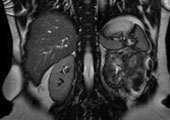

近日,燕达医院普外科主任李基业主任带领科室团队,成功为一位46岁的中年女性患者切除了腹膜后巨大脂肪肉瘤。这位患者5年内接受了2次腹腔肿瘤切除术,2个月前检查出肿瘤复发,就诊多家医院均因手术风险太大而被拒绝手术,zui终在燕达医院得到重生。